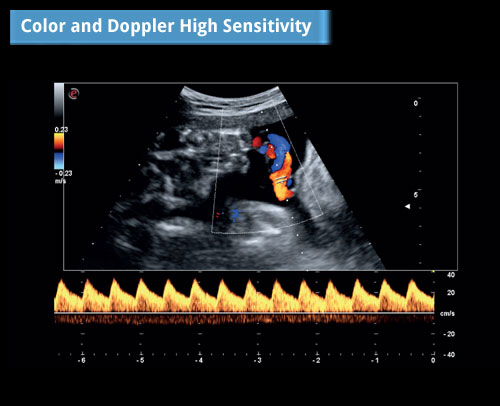

Vysoká citlivost barvy a dopleru: Triplexní režim na pupeční šňůře.